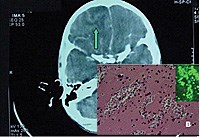

Hình ảnh amip tấn công não người. |

Tại BV Bệnh Nhiệt đới, bệnh nhân sốt 39 độ C, lơ mơ, cổ cứng, thở nhanh 30 lần/phút. Kết quả xét nghiệm soi dịch não tủy không thấy có vi trùng lao hay vi nấm gây viêm màng não nhưng lại có sự hiện diện của một loại amip. Sau đó, bệnh nhân vẫn sốt cao, 40 - 41 độ C, suy hô hấp, xuất huyết tiêu hóa và rơi vào tình trạng hôn mê sâu. Đến 23g ngày 31/7 bệnh nhân nhiều lần bị ngưng tim đột ngột, tử vong. Sau khi tử vong, Bệnh Nhiệt đới tiếp tục làm nhiều xét nghiệm và kết quả xét nghiệm sinh học phân tử PCR xác định nguyên nhân tử vong do “amip ăn não người”.